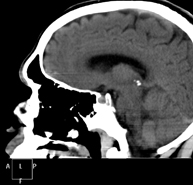

- Neurorradiología

- TC Cráneo

Prueba radiológica que consiste en obtener imágenes del cráneo de alta definición anatómica (tronco cerebral, cerebelo, cerebro, calota craneal, etc.), mediante el empleo de un equipo de TC (Tomografía Computarizada).Indicaciones: traumatismos, cefalea, trastornos de la memoria, pérdida de fuerza súbita en una extremidad o mitad del cuerpo.

Prueba radiológica que consiste en obtener imágenes del cráneo de alta definición anatómica mediante el empleo de un equipo de TC (Tomografía Computarizada). Indicaciones: cefalea, estudio de tumores, traumatismo craneal.